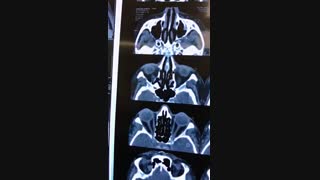

جراحی توده حدقه توسط دکتر رضا عرفانیان سلیم جراح و متخصص جراحی های چشم . شما می توانید جهت کسب اطلاعات بیشتر به وب سایتhttp://drerfanian.com مراجعه کنید .

جراحی توده حدقه